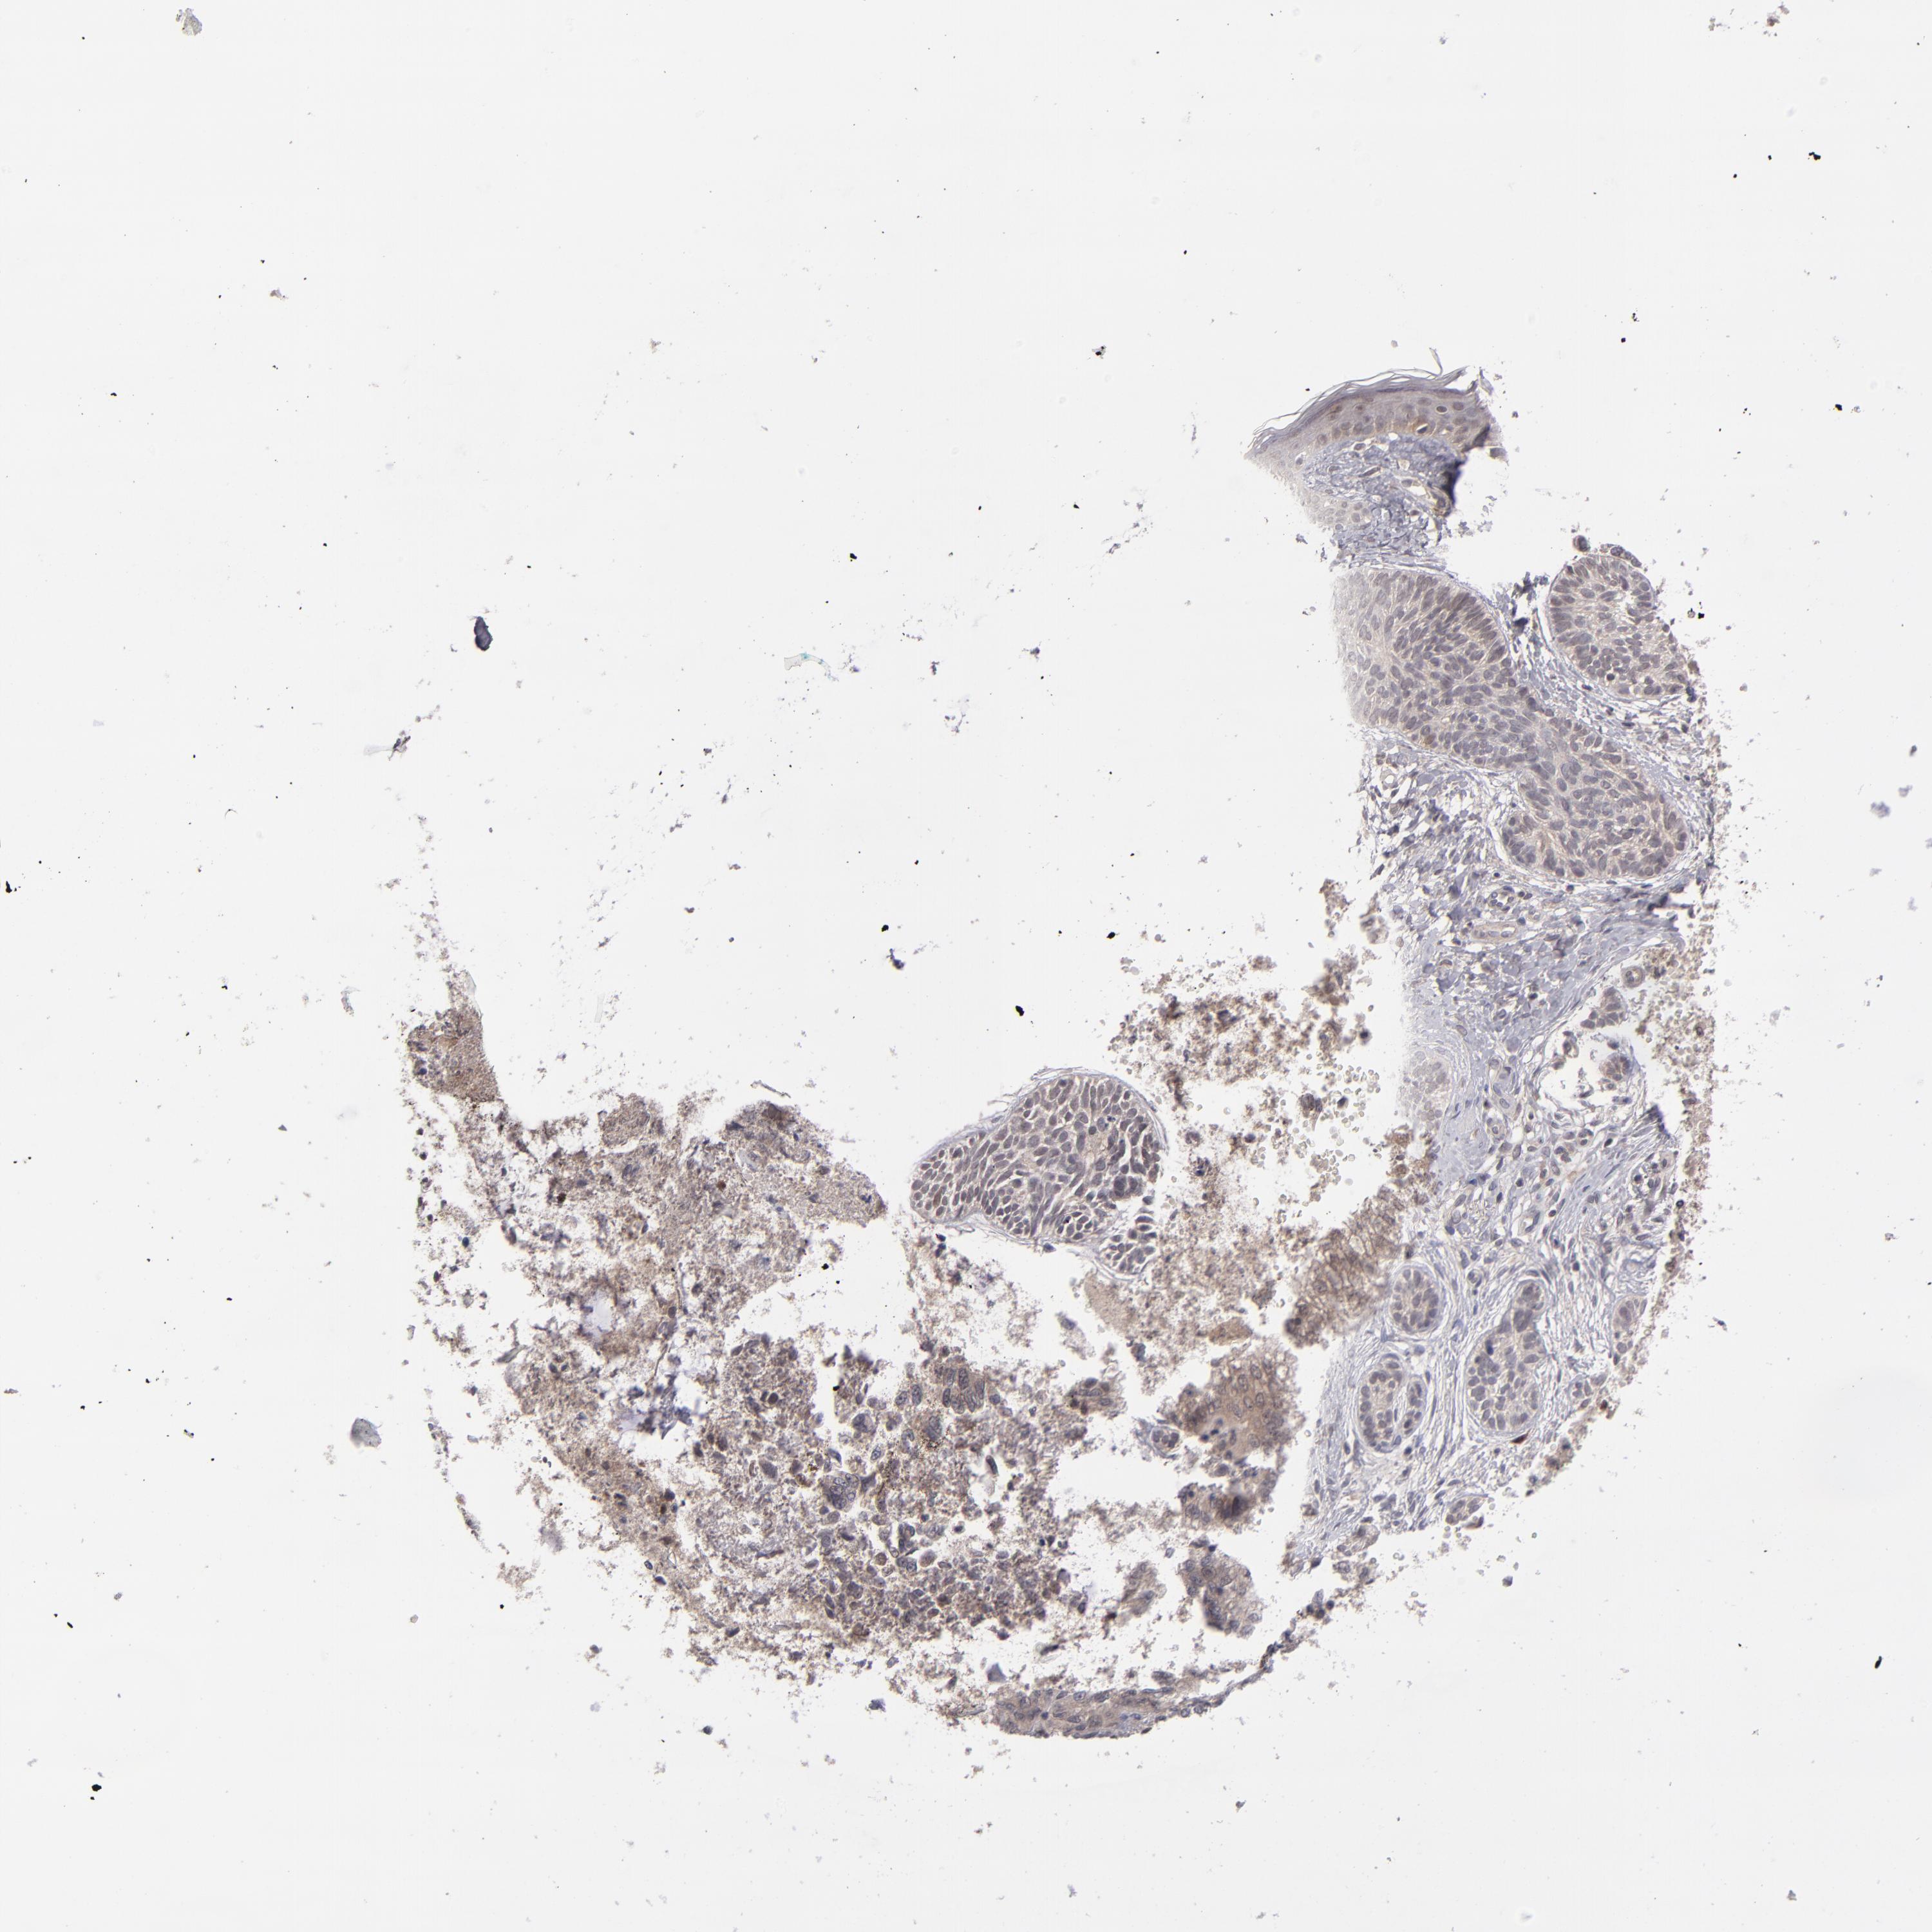

SKIN CANCER - Protein expressioni

A mouse-over function shows sample information and annotation data. Click on an image to view it in a full screen mode. Samples can be filtered based on level of antibody staining by selecting one or several of the following categories: high, medium, low and not detected. The assay and annotation is described here.

Antibody staining in the annotated cell types in the current human tissue is reported as not detected, low, medium, or high, based on conventional immunohistochemistry profiling in selected tissues. This score is based on the combination of the staining intensity and fraction of stained cells.

Each image is clickable and will lead to virtual microscopy that enables deeper exploration of all samples and also displays staining intensity scores, fraction scores and subcellular localization as well as patient and tissue information for each sample.

Antibody HPA074922

Antibody CAB002784

Staining

High

Medium

Low

Not detected

Intensity

Strong

Moderate

Weak

Negative

Quantity

>75%

75%-25%

<25%

None

Location

Nuclear

Cytoplasmic/membranous

Cytoplasmic/membranous,nuclear

Basal cell carcinoma

Squamous cell carcinoma, NOS